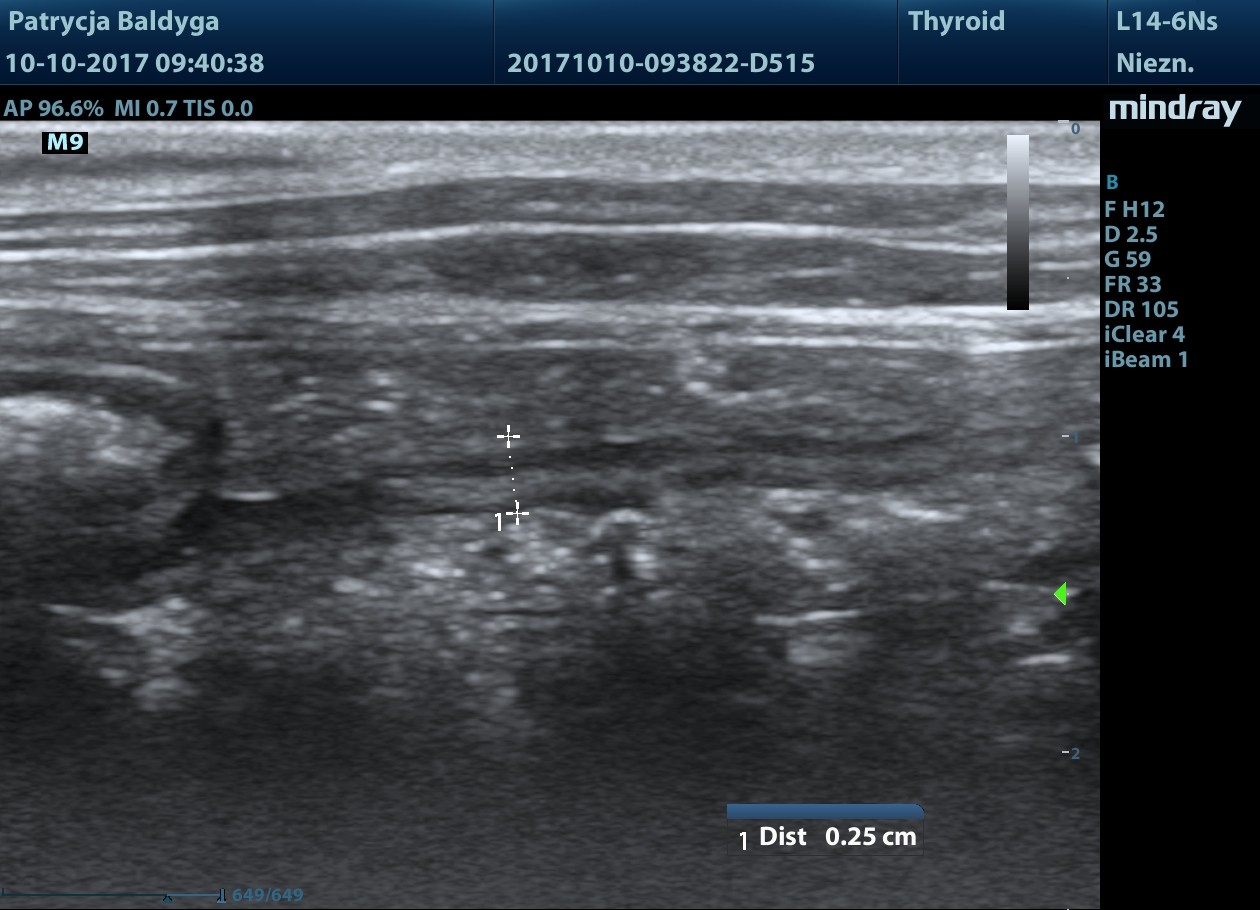

Śledziona niepowiększona, miąższ nieco niejednorodny zobecnością zawnękowo, przyściennie zmiany ogniskowej

słabo odgraniczonej, nieco hipoechogennej w centrum, hiper obwodowo, wielk. ok. 1,2 cm, mniejsza widoczna przedwnękowo, od pow. trzewnej, podtorebkowo śr. ok. 6-8 mm

niejednorodnie hipoechogenna, nieregularna, zmiany nie modulują brzegu narządu, bez cech patognomicznych.

Zmiany w śledzionie i jelicie grubym do różnicowania.